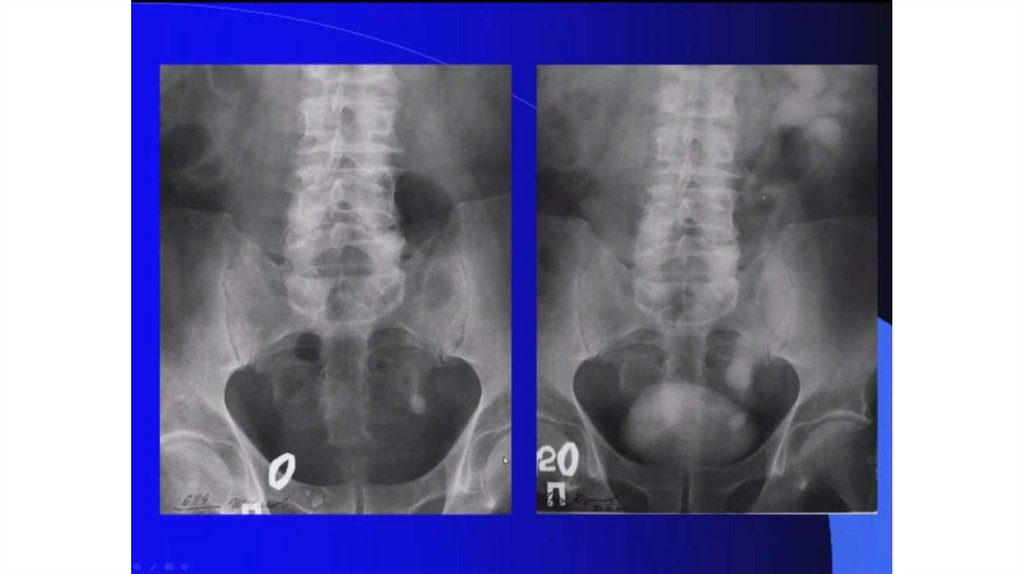

Мочекаменная болезнь. Мочекаменная болезнь и беременность

Мочекаменная болезнь